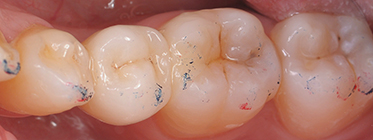

Quelles préparations postérieures ?

Le Choix des matériaux

Comment Assembler